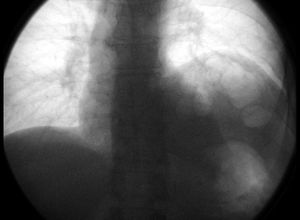

5. 추가 사진